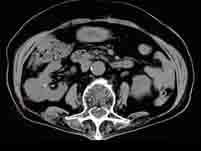

诊断肾肿块最好的检查方法是()A.B超B.CTC.IVUD.腹平片E.肾图

问题 诊断肾肿块最好的检查方法是()

选项 A.B超 B.CT C.IVU D.腹平片 E.肾图

答案 B